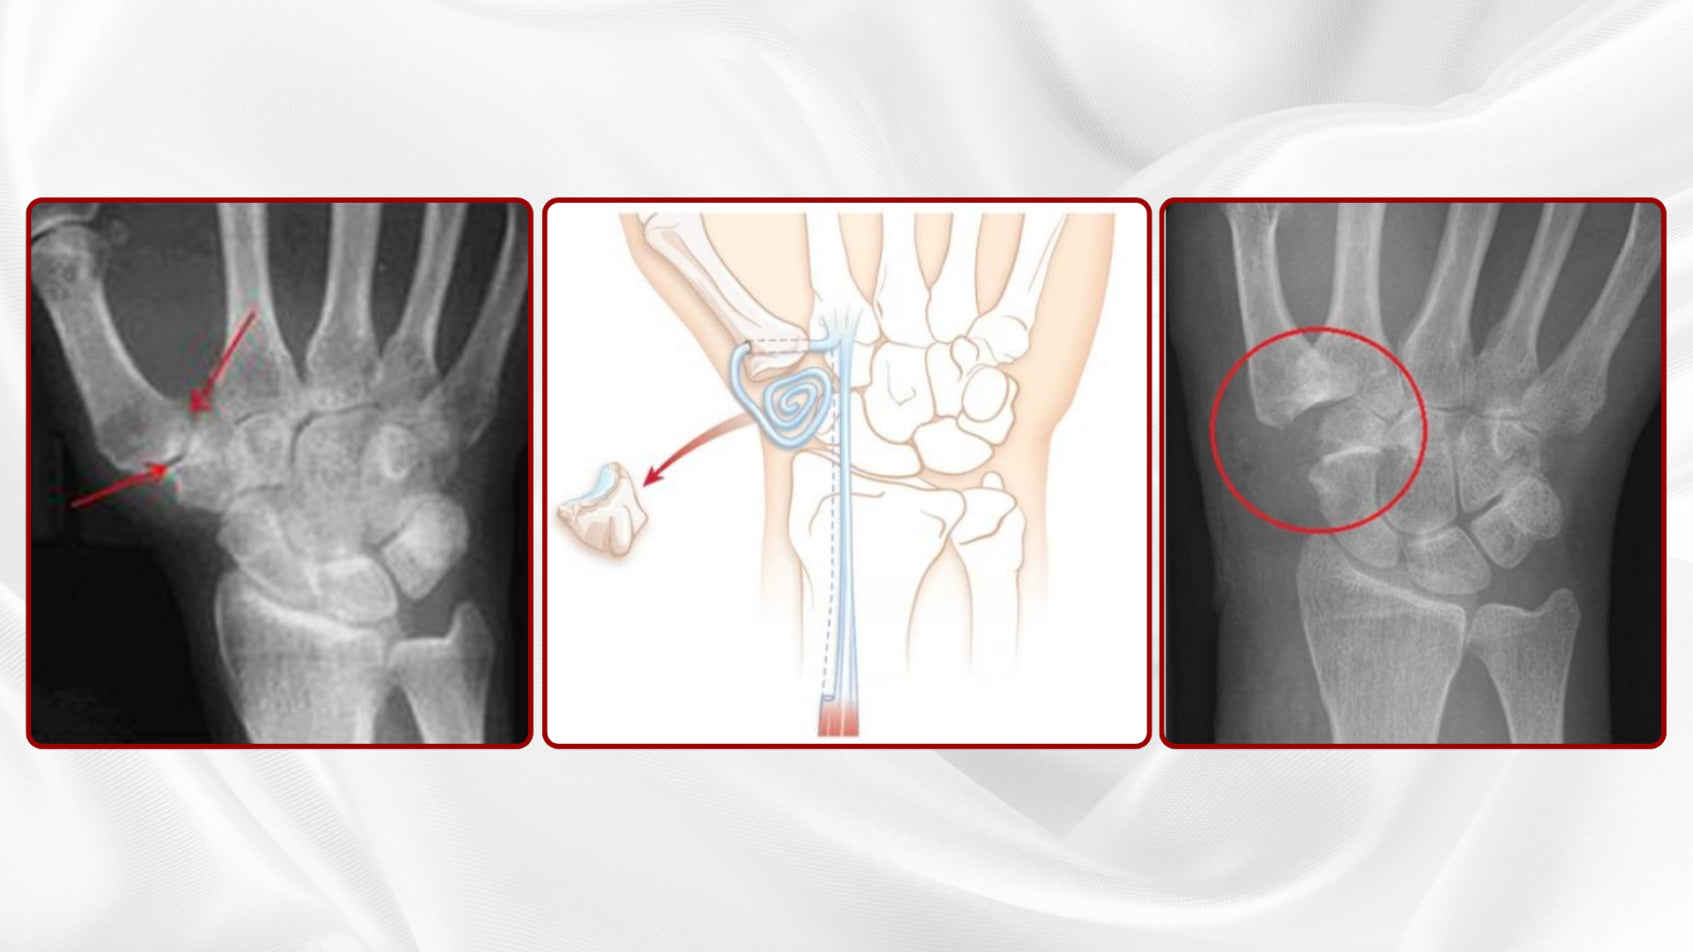

Joint changes

Joint changes (Osteoarthritis in the Hand area)

Osteoarthritis is the typical wear and tear of the joints and a natural consequence of our aging process.

The aging process of the joints is a combination of external (heavy work, …..) aging and the internal (genetic, hormonal changes, …) aging process.

Key symptoms of joint aging in the hand area are a combination of

- Pain

- Functional impairment

- aesthetic impairment

In almost 70% of the over 65 year olds, signs of arthrosis can be detected in the x-ray. These do not necessarily have to lead to complaints. However, half of all 60-year-olds complain about the typical arthrosis symptoms.

Thumb

The metatarsophalangeal joint often shows age-related joint changes (rhizarthrosis), which lead to typical swelling, misalignment, (stress) pain and functional restrictions (“wringing out a cloth” becomes painful).

Finger

The finger end joints (Bouchard arthrosis) and finger middle joints (Heberden arthrosis) often show age-related joint changes, which lead to typical swelling (“rings no longer fit”), malpositions, (stress) pain and functional restrictions.

As arthrosis progresses, joint movements become permanently painful – especially under stress – the joint may crunch and/or the mobility of the joint may be restricted. In the last stage of joint wear and tear, the joints also hurt at rest, which, among other things, can make restful sleep impossible.

- Arthroplasty (Link→Resection-Suspension Arthroplasty of the CMC I Joint according to EATON-LITTLER)